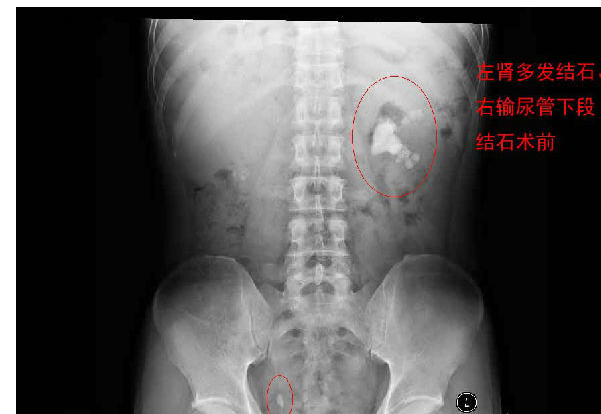

每天早上手術(shù)間響起泌外醫(yī)生們特有的交談聲音和機(jī)器們互相的運(yùn)轉(zhuǎn)聲交替成了一道熟悉不變的旋律,從手術(shù)室護(hù)士擺著各種專用體位,推著各種器械,液體進(jìn)進(jìn)出出,醫(yī)生們應(yīng)用著各種碎石手段消滅石頭,利用氣壓彈道、激光、超聲等碎石工具,把結(jié)石擊碎取出,一陣忙碌的節(jié)奏。泌尿外科的手術(shù)時(shí)間都不長(zhǎng),每天手術(shù)例數(shù)又多,你就會(huì)看見(jiàn)這么一群人來(lái)來(lái)回回,醫(yī)生護(hù)士還是那么個(gè),病人都換了無(wú)數(shù)。最長(zhǎng)一次從早上8點(diǎn)到隔天凌晨2點(diǎn)才結(jié)束手術(shù),回到家就立馬睡覺(jué)都顧不上吃飯?,F(xiàn)在手術(shù)間正做著一臺(tái)經(jīng)皮腎鏡下碎石取石術(shù),這是我們醫(yī)院泌外科的王牌。

經(jīng)皮腎鏡取石術(shù),就是在腰部建立一條從皮膚到腎臟的通道,通過(guò)這個(gè)通道把腎鏡插入腎臟,英文簡(jiǎn)寫為PCNL。經(jīng)皮腎鏡取石術(shù)是腎結(jié)石治療的現(xiàn)代微創(chuàng)技術(shù),我院在惠州率先開(kāi)展此項(xiàng)技術(shù),現(xiàn)在每年進(jìn)行數(shù)百例手術(shù),基本上已經(jīng)淘汰了開(kāi)放手術(shù)取石。經(jīng)皮腎鏡取石術(shù)是一項(xiàng)技術(shù)性非常強(qiáng)的手術(shù)。我們知道,腎臟是血管非常豐富的器官,腎臟血流占心臟排出血量的1/4。既要盡量避免出血、又要努力取凈結(jié)石、還要保護(hù)腎臟功能,這需要非常精細(xì)的手術(shù)技術(shù)。從某種程度上說(shuō),這個(gè)手術(shù)要比治療腎癌的腎切除術(shù)難度大很多。傳統(tǒng)的“開(kāi)刀取石”的方法,需要在腰部做一個(gè)的大切口,切開(kāi)腰部的肌肉,把腎臟分離出來(lái),在腎盂或腎實(shí)質(zhì)切開(kāi)一個(gè)小口,將結(jié)石取出來(lái)。這種方法損傷大、出血較多、痛苦重、恢復(fù)慢。通常手術(shù)后需要住院7天以上。因?yàn)槭中g(shù)切口大,不但皮膚不美觀,而且手術(shù)后患者的體力受影響比較大。與開(kāi)放手術(shù)相比,經(jīng)皮腎鏡取石術(shù)具有損傷小、痛苦輕、取石徹底、恢復(fù)快等優(yōu)點(diǎn)。腰部的切口通常小,因?yàn)椴磺虚_(kāi)肌肉,不但不影響美觀,而且手術(shù)后對(duì)勞動(dòng)力幾乎沒(méi)有影響。手術(shù)后住院時(shí)間也明顯縮短。與腹腔鏡取石相比,經(jīng)皮腎鏡取石術(shù)對(duì)腎臟及周圍的結(jié)構(gòu)影響小,不影響以后的各種腎臟手術(shù)。與體外碎石相比,它的治療周期短、效果立竿見(jiàn)影,對(duì)腎功能的影響也較小。(手術(shù)室/麻醉科 阮伊莎)